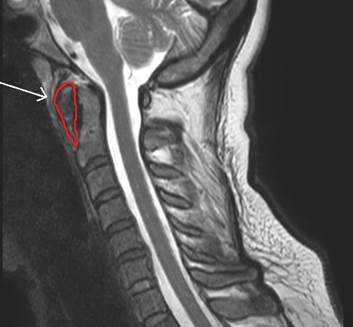

При наличии дегенеративных изменений определяли частоту, приблизительный возраст наступления и степень изменений, проводили сверку с общей статистикой дегенеративных изменений в атланто-аксиальных суставах. Произведены сравнительная анатомия конфигурации частей атланта и осевого позвонка в основной и контрольной группах, измерение сагиттальных размеров толщины передней дужки атланта на различной удаленности от медианы (переднего бугорка). Измеряли переднезадние и вертикальные размеры сечения в сагиттальной плоскости, отступив на 2 мм от медианы латерально (рис. 3).

Рис. 3. Сагиттальные томограмммы Т1 и Т2ВИ (красный контур сагиттальной плоскости сечения расщепленной передней дужки атланта)